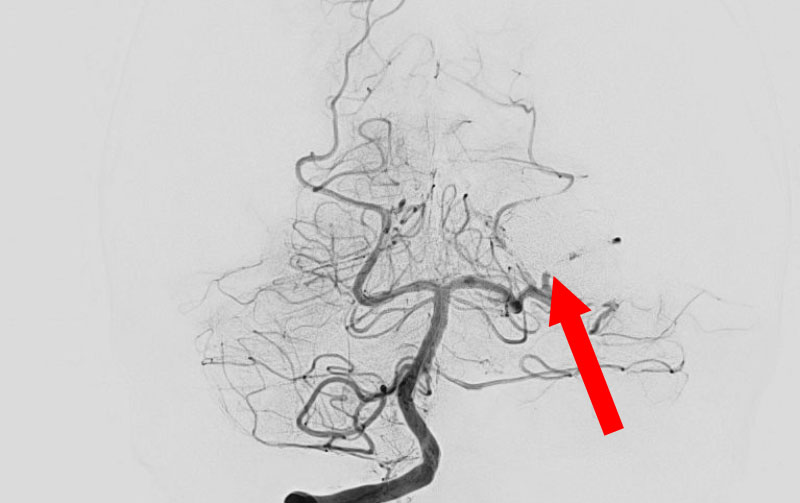

くも膜下出血

左中大脳動脈瘤破裂

40代

救急外来

No.1596 手術前